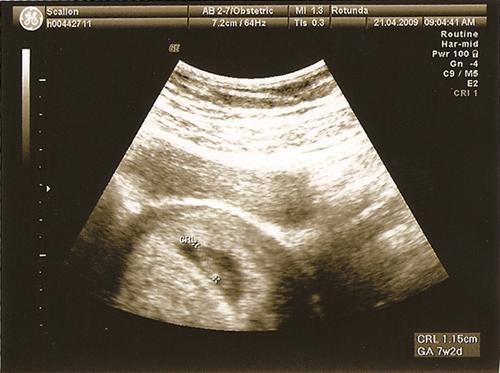

7.2 weeks, just a little munchkin